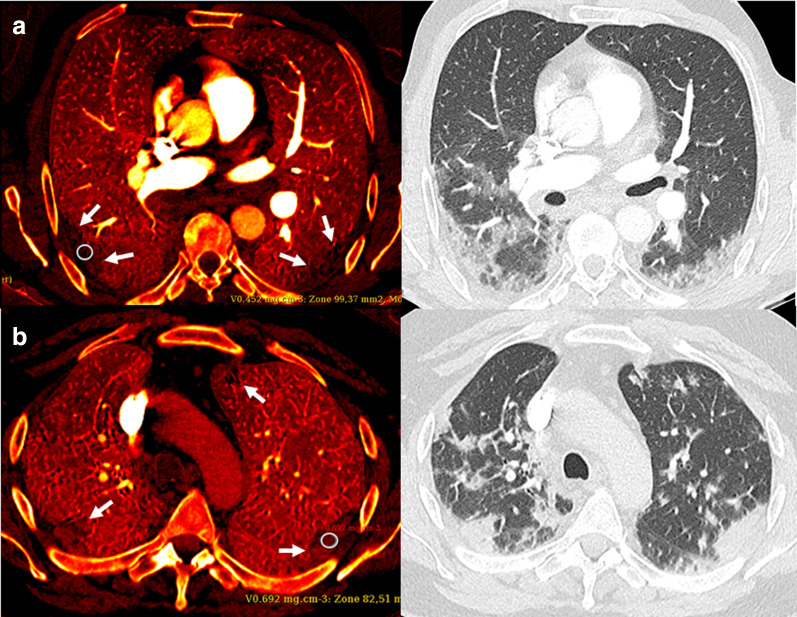

Fig. 2.

a 66-year-old male with COVID-19 related pneumonia at hospital day 7. A rt-PCR assay confirmed the diagnosis. DE-CTPA was performed for increased D-dimer (640 ng/mL) and oxygen requirement levels. Heterogeneous iodine distribution (PD +) is seen with sub-pleural perfusion defects (iodine map, left) partially matching the consolidations in the lower lobes (conventional lung images, right). Iodine concentration was measured at 0.452 mg/cm3 using a 1 cm2 ROI within the circle and at 0.873 mg/cm3 within the normal-appearing parenchyma. b 57-year-old-male with a rt-PCR confirmed COVID-19 pneumonia also at hospital day 7. The D-dimer level was increased at 1160 ng/mL. Heterogeneous perfusion defects (PD +) are seen in the sub-pleural areas (iodine map, left), partially matching the lung opacities (right). Iodine concentration was measured at 0.692 mg/cm3 within the circle and at 0.928 mg/cm3 within the normal-appearing parenchyma